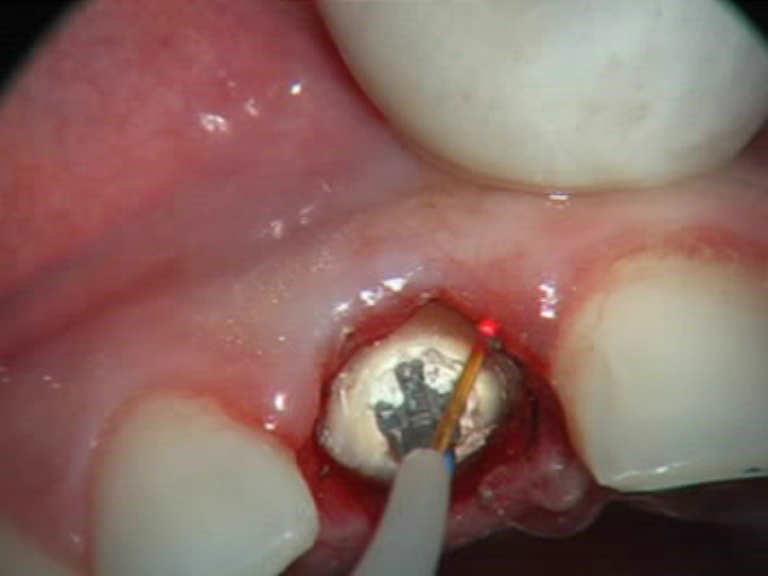

Dott. Stefania Cristalli

Laser Setting

Diode Laser 810nm

Power: 1,5 Watt, CW

Fibre 200 micron

Break under the gingival edge. A gingivectomy is made with a diode lasers 810nm.